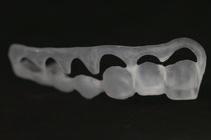

crown lengthening guide may be designed, 3D-printed in Temp Premium Flexible transparent resin (Zirkonzahn Srl, Gais, Italy), post-processed ( Figure 2 ) and subsequently tried in the patient’s mouth.

FIGURE 2: Based on the diagnostic findings of the 3D virtual feasibility study, a fully tooth-supported and fully digitally fabricated surgical guide may be developed via a process of computer-aided design and computer-aided manufacturing (CAD/CAM). The guide indicates the proposed gingival margin location as well as the proposed incisal edge and cusp height locations.